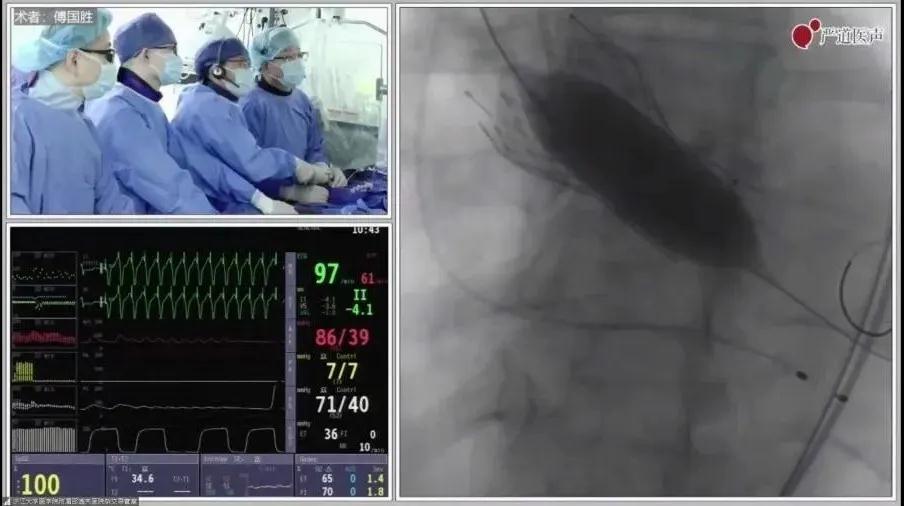

在第15届“西子心血管联席会议”期间,大会主席、浙江大学医学院附属邵逸夫医院傅国胜教授带来了一场精彩的TAVR教学手术演示。

傅国胜教授TAVR团队手术演示

傅国胜教授团队(左三俞飞成医师等)手术中